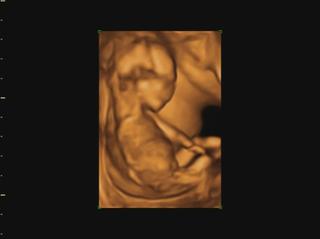

už som objednaná aj na 3D do KE... konečne môžem kľudne spávať 😀 😀 😀

@veronika1417 medzi 3d a 4d nie je skoro žiadny rozdiel, takže všade kde robia 3d robia aj 4d, lebo to štvrte D znamena čas,4d-real time, že mimi vidiš v realnom čase ako sa hybe.čiže stale je to 3d-trojdimenzionalne videnie babatka v 4d-realnom čase 😉

@luci66 juuuj Ty mas ake super informacie 🙂 to som vobec nevedela ze sa meria nosova kosticka a sijove prejasnenie, ten doktor na sone je taky dilino cely cas je ticho len tam znudene sedi a mna ide slaktrafit a trpnem ci je vsetko v poriadku ☹ ja som si veru sono uzila velakrat lebo sme dost lezali v nemocnici ale uz je to oki. Teraz uvidim miminko az 30.6 co je strasne daleko ☹ to uz budeme v 20 tyzdni 🙂 takze aj obrazok by mal byt uz kraaasny 🙂 mozno si dam aj ten 3D viem ze v Ba robia aj 4D ale v NR len 3D